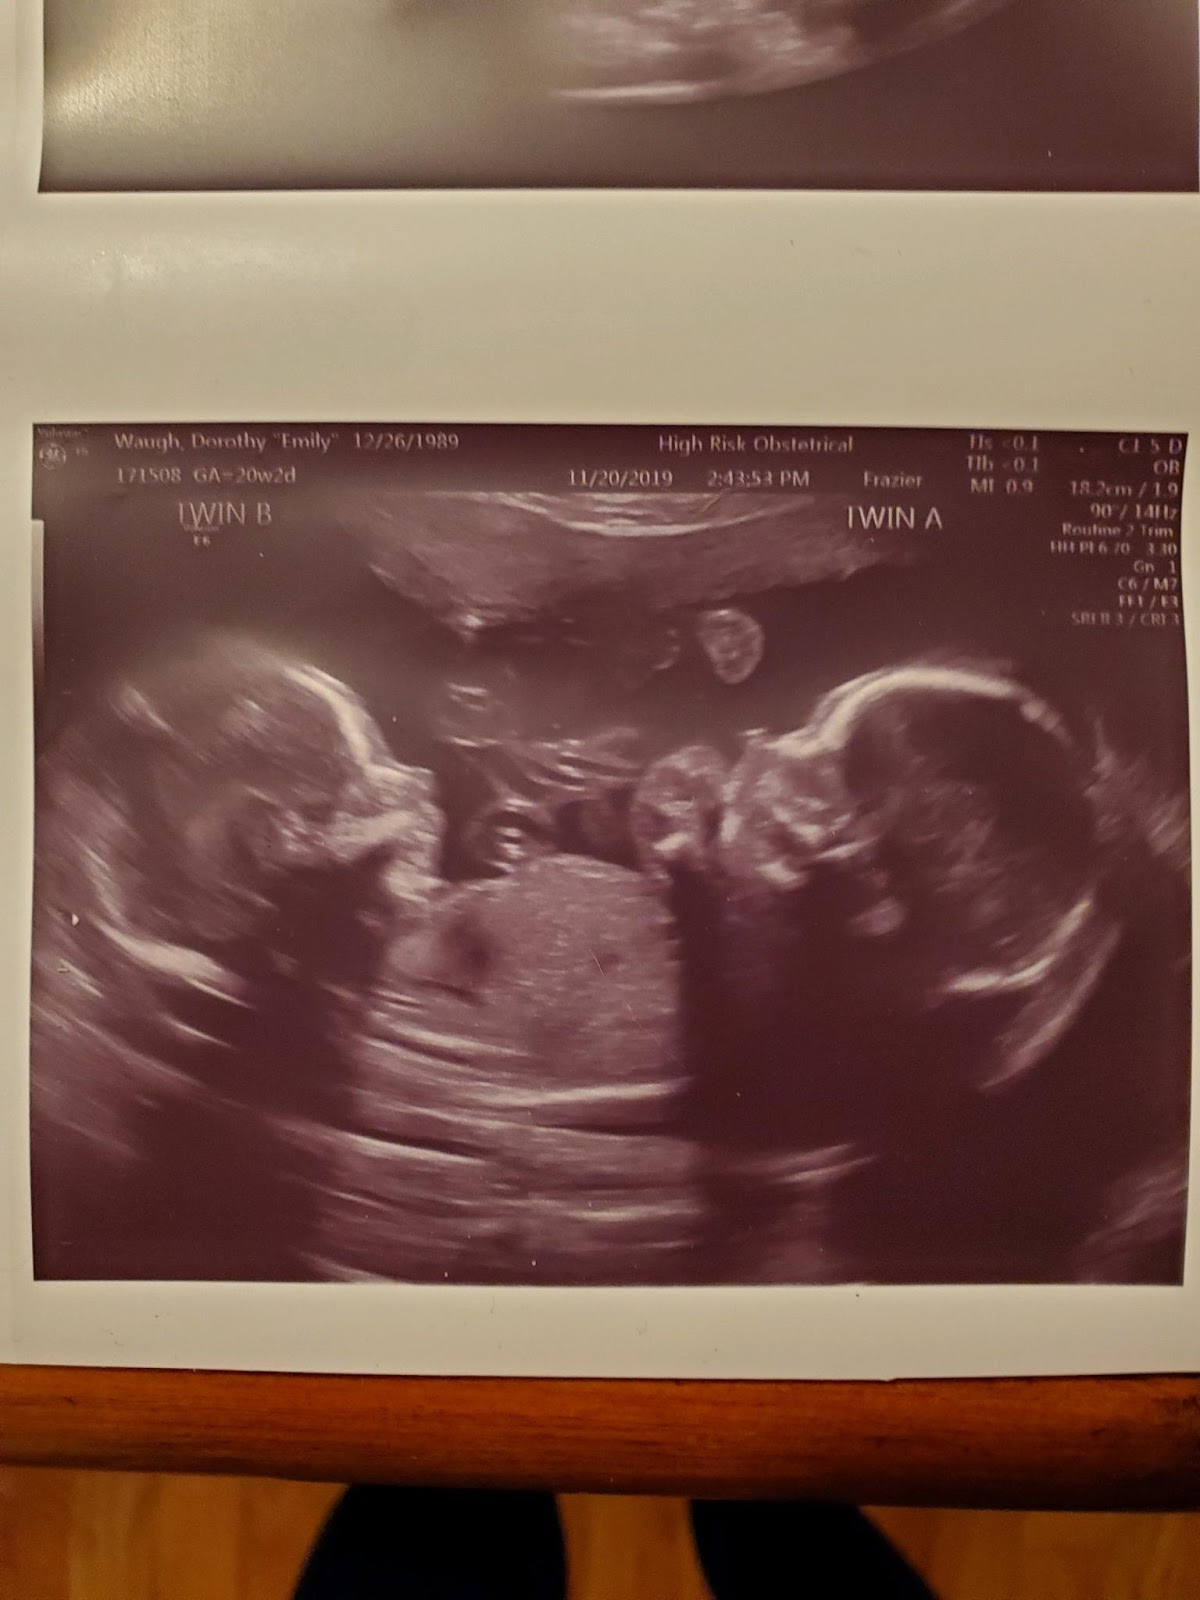

Later that evening, youngest daughter, called. She is expecting identical twin boys in April. She and her husband along with their son, Blake, who will be two in January wanted to come down. They had been to her doctor appointment, and they wanted to eat dinner with me. Since she is having twins, the twins are in the same placenta but in different sacs, she sees a specialist every other week.

Before dinner, she explained to me that both boys are doing great...they are growing and are the same size and she will return in two weeks. After dinner, she showed me the pic of the ultrasound and told me they had decided on names. Twin A 's name is Aiden Charles (after my dear Charlie) and Twin B's name is Liam Grant (Liam comes from William and William was my father's name who passed away shortly after I got married with cancer). The tears flowed again well, more like heavy, heavy tears. I love the names. She said she had thought about her dad all day and I told her I had to. She was sad that he won't be here to see them, But I told her that Charlie hand picked them in Heaven and sent them to her and Kenneth. And just like I tell Blake about his Buddy (Charlie was called Buddy not Papaw) I will make sure these two boys will know what a special person their Buddy was.